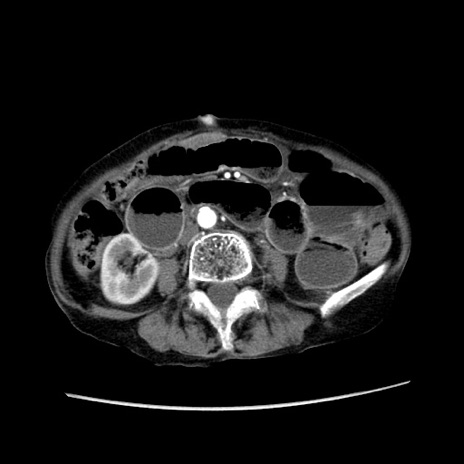

症例25(横断像)

【症例】80歳代女性

【主訴】胸のつかえ感

【現病歴】約9時間前に食後から胸のつかえた感じあり、嘔吐あり、来院。

【既往歴】胃癌(全摘)、胆摘、虫垂炎

【身体所見】心窩部に圧痛あり、反跳痛なし。

【データ】WBC 5700、CRP 0.05